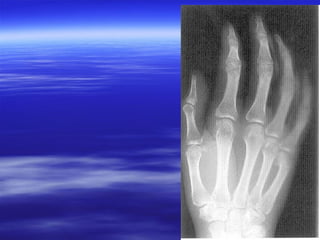

Sharp edges image

Unsharp edges image

Radiographs small bone with shot embedded in it